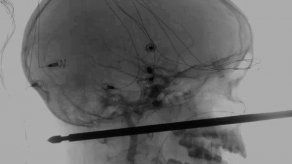

Niño sobrevive luego que brocheta le atraviesa la cabeza